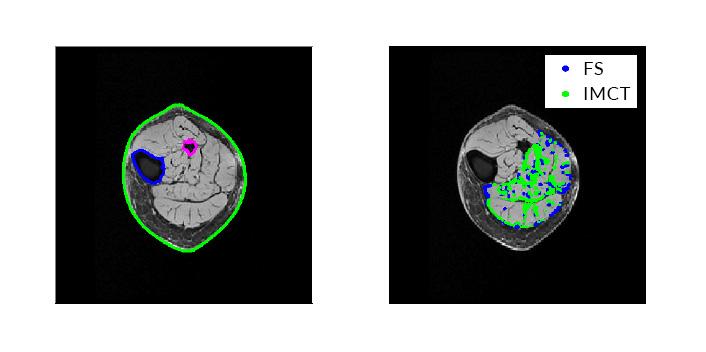

Engineers at the University of California, San Diego, have completed the first comprehensive numerical simulation of skeletal muscle tissue using a method that uses the pixels in an image as data points for the computer simulation—a method known as mesh-free simulation.

Using the mesh-free method cuts back on the amount of time for the process of generating the simulation model because researchers don't have to build a mesh for the structure they're trying to simulate, said Ramya Rao Basava, the lead Ph.D. student on the study.

For this study, researchers in Chen's group used Magnetic Resonance and Diffusion Tensor images for the mesh-free simulation. The images were obtained through the Department of Radiology at UC San Diego. The image data acquired was from 10 volunteers between the ages of 20 to 90. The younger subjects were mostly in their 20s and 30s, the older ones mostly in their 80s.